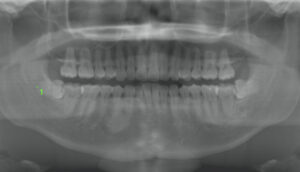

| 治療内容 | 当院で矯正治療を行う患者様で、矯正前に違和感があるので左上の親知らずの抜歯を希望されました。 かなり深い位置に埋伏していたのと、根が大きく曲がっていたので歯肉を切開し、歯の頭を分割して抜歯しました。30分ほどで抜歯は終了いたしました。 |

| 治療内容 | 痛みなどの症状はなく、歯肉の中に完全に埋まっている歯でしたが親知らずのせいで歯並びが悪くなっている気がするとのことで抜歯を希望されました。 一見簡単そうに見えますが骨にも埋まっており、レントゲン写真では見えない位置で歯根が2つに別れていたため、歯根も分割して抜歯しました。あらかじめCTを撮影していたため、分割も予測でき、15分で抜歯終了いたしました。 |